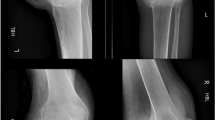

Many individuals with spinal cord injury (SCI) rely on wheelchairs as their primary mode of locomotion leading to reduced weight-bearing on the lower extremities, which contributes to severe bone loss and increased risk of fragility fractures. Engaging in a walking program may reverse this vicious cycle, as this promotes lower extremity weight-bearing and mobility, which may reduce bone loss and fragility fracture risk. However, fragility fracture risk associated with the use of wearable robotic exoskeletons (WREs) in individuals with SCI needs consideration. A 35-year-old man with chronic complete sensorimotor SCI (neurological level = T6) and low initial bone mineral density enrolled in a 6- to 8-week WRE-assisted walking program after successfully completing an initial clinical screening process and two familiarization sessions with the WRE. However, after the first training session with the WRE, he developed bilateral localized ankle edema. Training was suspended, and a CT-scan revealed bilateral calcaneal fractures, which healed with conservative treatment over a 12-week period. Opportunities for improving clinical screening and WRE design are explored. The relevance of developing clinical practice guidelines for safe initiation and progression of intensity during WRE-assisted walking programs is highlighted. This case of bilateral calcaneal fractures illustrates that aiming for “zero risk” during WRE-assisted walking programs may not be realistic. Although WREs are a relatively new technology, current evidence confirms their potential to greatly improve health and quality of life in individuals with chronic SCI. Hence, ensuring their safe use remains a key priority.